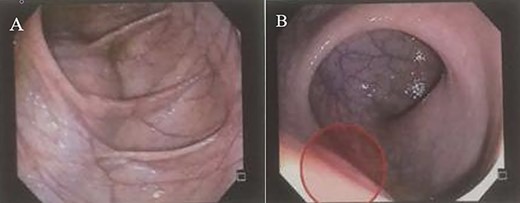

A 28-year-old female patient with a surgical history of excision of a pilonidal cyst 2 years ago presented with local discomfort when sitting for 6 months. The examinations performed suggested a tailgut cyst, and the principal differential diagnosis was a recurrence of the pilonidal cyst. Abdominal and pelvic MRI identified an extensive collection occupying soft tissues in the sacrococcygeal region, extending anteriorly under the sacrum and coccyx to the retrorectal space on a closed end, apparently without continuity with the subcutaneous mesh in the buttocks region. It had thin and regular walls and partial parietal enhancing of the rectosacrococcygeal portion, measuring 9.9 × 7.9 × 3.9 cm, with an estimated volume of 158 ml. The collection exerted a modest compressive effect on an adjacent posterior rectal wall but maintained a well-defined cleavage plane (Fig. 1). Colonoscopy showed extrinsic compression in the posterior and right lateral wall of the inferior rectum, above the puborectalis muscle (Fig. 2). Rectal ultrasonography showed multicystic content in the retrorectal space (Fig. 3). The patient underwent a complete resection of the tailgut cyst via posterior intergluteal access. She was discharged on the first postoperative day, with no complications or sequelae and no evidence of recurrence until 18 months of postoperative follow-up.

(A and B) MRI shows a large collection in the rectosacrococcygeal region, extending anteriorly to the retrorectal space.